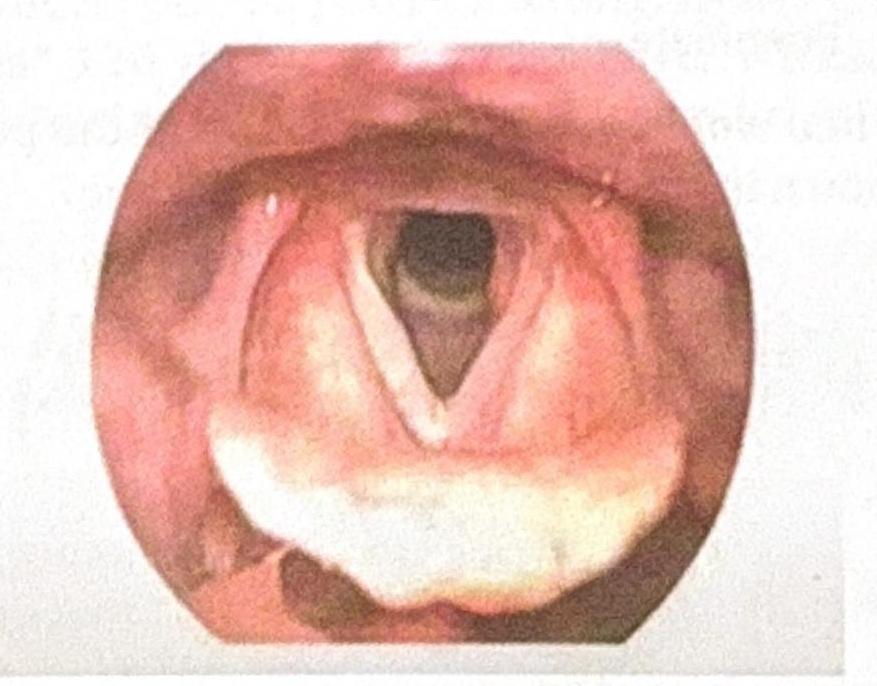

What is the grade of laryngeal view?

Explanation: ***Grade I*** - In a **Grade I laryngeal view**, a **full view of the glottis** (vocal cords) is achieved during laryngoscopy. - This provides optimal conditions for endotracheal intubation, as seen in the image where the entire opening to the trachea is visible. *Grade II* - A **Grade II view** means only a **partial view of the glottis** is obtained, often with only the posterior commissure visible. - The anterior portion of the vocal cords may be obstructed by the epiglottis or other structures, making intubation more challenging. *Grade III* - **Grade III** indicates that only the **epiglottis** is visible, with no part of the glottis or vocal cords being seen. - Intubation is significantly more difficult in this scenario and often requires special techniques or adjuncts. *Grade IV* - A **Grade IV view** is the most difficult, where **neither the epiglottis nor the glottis** can be visualized. - This implies that only the soft palate or base of the tongue is seen, representing a very challenging airway.

What is the staging system used for the condition seen in the patient after a history of intubation, as shown in the image?

Explanation: ***Cormack and Lehane*** - The **Cormack and Lehane classification** system is used to grade the view of the **larynx** during **direct laryngoscopy** for intubation. - Given the history of intubation and the image showing the laryngeal view, this system is the most appropriate for staging the visual difficulty or success of intubation. *AJCC* - The **American Joint Committee on Cancer (AJCC) staging system** is primarily used for **oncological staging**, classifying the extent of cancer. - It is not relevant for assessing the view of the larynx during intubation. *TNM* - **TNM staging** (Tumor, Node, Metastasis) is a widely used system for classifying the **progression of cancer**. - This system is specific to cancer staging and is not applicable to the assessment of airways for intubation. *Radkowski* - The **Radkowski staging system** is used to classify **pediatric subglottic stenosis**, a narrowing of the airway below the vocal cords. - While it deals with airway issues, the question focuses on the view during intubation, not the severity of subglottic stenosis, and the image does not specifically point to this condition.